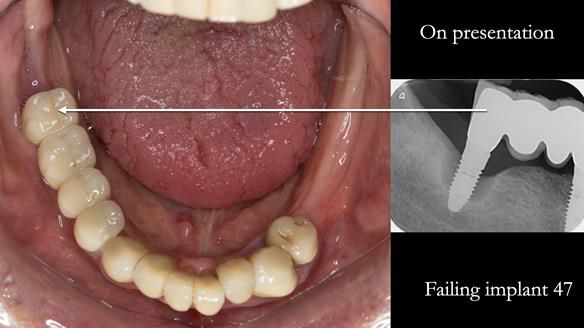

The starting point

We began with the lower jaw.

A posterior implant 47 had lost integration and was infected. This was removed.

Ken did not want further implant surgery.

Instead, we made a Scandinavian-style, metal-based lower RPD.